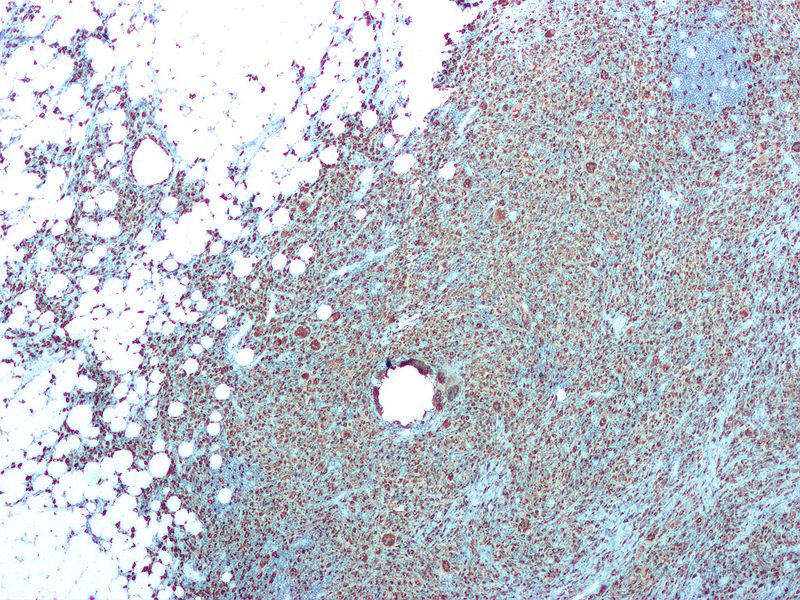

Tubule atrophy and interstitial fibrosis as a result of repeated bouts of acute pyelonephritis.

Chronic pyelonephritis results in cortical scarring with blunted calyces.

Histology of chronic pyelonephritis may show atrophic tubules with eosinophilic proteinaceous debris that resembles thyroid follicles termed “thyroidization” of the kidney.